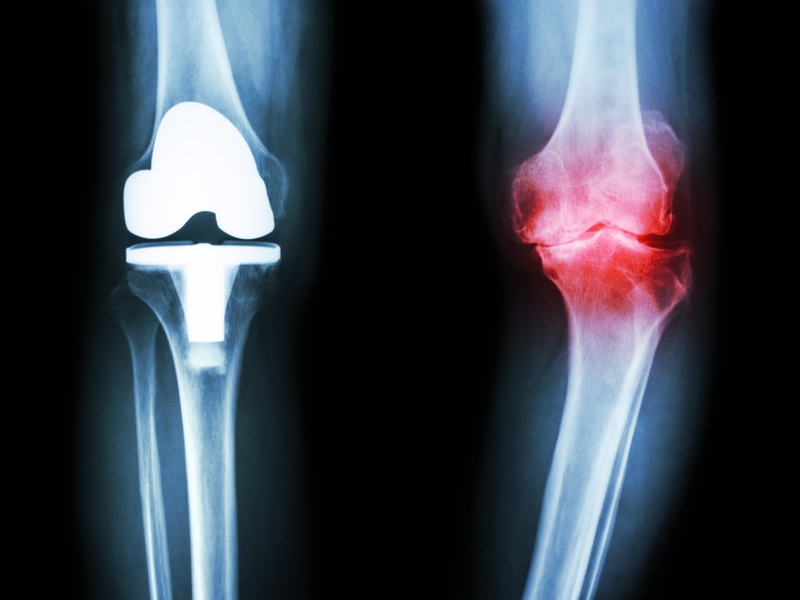

Thoái hóa khớp gối là một trong những căn bệnh phổ biến nhất hiện nay. Cùng tìm hiểu ngay về tiêu chuẩn chẩn đoán thoái hóa khớp gối qua bài viết dưới đây của Nhà thuốc Long Châu nhé!

Tiêu chuẩn chẩn đoán thoái hóa khớp gối là yếu tố quan trọng giúp các bác sĩ xác định được chính xác tình trạng bệnh. Từ đó, đưa ra được những chỉ định điều trị chính xác. Vậy tiêu chuẩn chẩn đoán thoái hóa khớp gối hiện nay là gì? Hãy cùng Long Châu tìm hiểu thông qua bài viết dưới đây nhé!

Thoái hóa khớp gối là kết quả của việc sụn và khớp xương ở đầu gối bị hủy hoại, khiến cho khớp gối bị biến dạng, thay đổi hình dáng, hóa sinh và cơ sinh học của tế bào sụn.

Khi nghi ngờ bệnh nhân bị thoái hóa khớp gối, bác sĩ sẽ chỉ định người bệnh thực hiện một số các phương pháp chẩn đoán như: Siêu âm, chụp X-quang, chụp cộng hưởng từ MRI,... Đây đều là những phương pháp chẩn đoán bằng hình ảnh, giúp bác sĩ dễ dàng nhìn nhận được những biểu hiện của căn bệnh này.